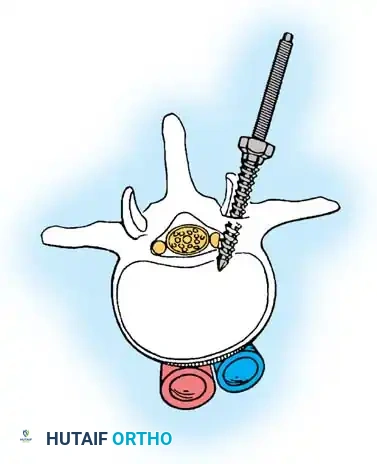

Biomechanics of Bone Grafting

Bone graft incorporates most effectively under compressive loads and is biologically disadvantaged in environments of distraction. Therefore, in scoliosis correction, if autogenous bone is limited, it should be preferentially concentrated on the concave side of the curve, which is subjected to compressive forces, rather than the convex side, which experiences tension. Furthermore, the farther the fusion mass is placed from the instantaneous axis of rotation, the more effectively it will neutralize movement across that axis.